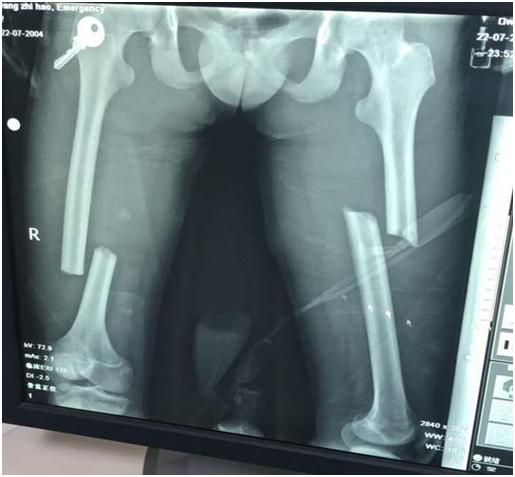

近日,我们医院骨二科收治了一名危重而特殊的患者,患者16岁,身材矮小,因车祸导致双侧股骨干骨折,作为青少年骨折患者,身体尚未发育成熟,骨骺线未完全闭合,如果采用传统的切开复位钢板内固定的手术方式,伤口较大,剥离骨膜,较容易破坏血运,出现骨折延迟愈合,甚至不愈合、感染等并发症,而且必将影响患者的生长发育,如何保障孩子能够健康成长,又能以最小的创伤恢复病情,成为摆在威海市中医院骨二科王钦楠主任和团队面前的一道难题。

双侧股骨干骨折术前照片

经过骨二科全科人员的商讨后,全麻下行闭合复位髓内钉内固定术的手术方案基本确定。但就国内目前而言,有关髓内钉固定治疗骨骼未成熟的股骨干骨折的疗效研究的样本较小。而且,孩子身高仅160cm,形体偏瘦,测量股骨髓腔最细处约6-7mm,而成人最细髓内钉髓直径大约9mm,无法使用。王钦楠主任积极联系厂家及器械公司,适合的髓内钉终于及时到位,在克服一系列困难及相关科室的支持下,作为威海市首例、山东省第二例同类手术,顺利完成,患者目前已开始负重功能锻炼,病情恢复良好。